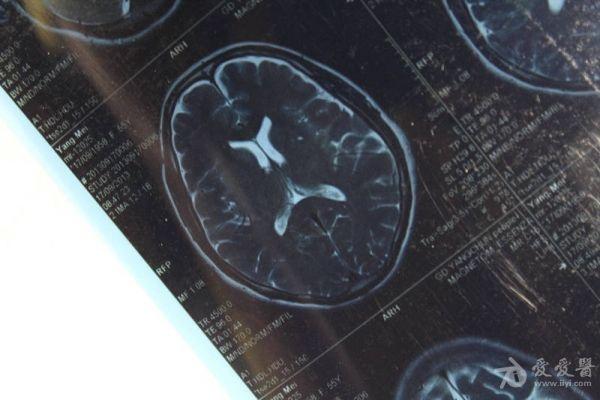

脑部占位病变CT,MRI图片,请帮忙诊断

最近感图样,无其它脑病病史

考虑脑膜瘤!!

磁共振没有平扫,增强矢状位没找到病灶。像脑膜瘤。

图片不是很清楚,应该是脑膜瘤!